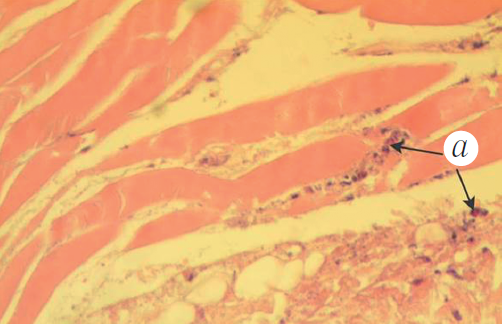

In the control samples, obtained from the left scapula during surgery, we observed more pronounced edema, hemorrhagic foci, and intact bone tissue and periosteum (Figure 4).

Fig. 4. Histological preparation of the left scapula of a rabbit, an acute experiment: a – perimysial edema; b – hemorrhages